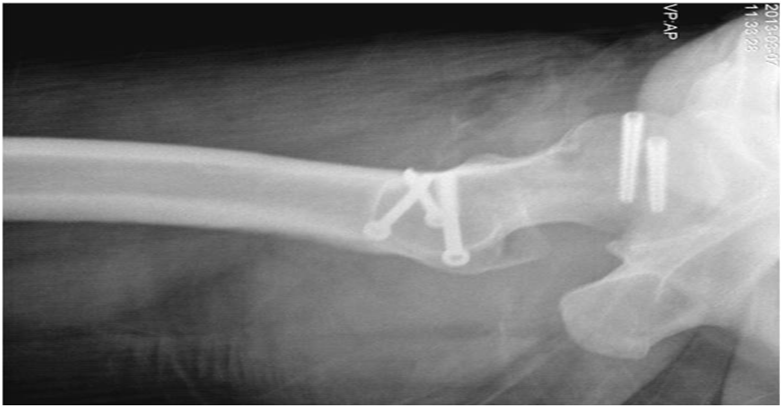

We decided to perform open reduction and internal fixation immediately. To preserve posterior vascularity of femoral head, we approached hip joint anteriorly after careful flip osteotomy of greater trochanter. As retracting osteotomized greater trochanter, we were able to find fractured femoral head and its large fragment (Figure 3A). Fractured fragment was measured about 45mm in diameter and was a large part of anteromedial femoral head involving half of ligamentum teres (Figure 3B & 3C). It was possible to perform accurate reduction and rigid fixation of fractured fragment with two Acutrak screws (40mm and 35mm, Acumed®, USA) and careful reduction of dislocated hip was performed (Figure 4A & 4B). Finally we reattached and fixed the osteotomized greater trochanter with three screws. Postoperative simple radiogram and computerized tomogram showed well fixed fracture fragment with mild residual indentation on anterosuperior femoral head (Figure 5A–5C). On postoperative one day, he could ambulate with wheelchair. One week later, he was permitted to walk with crutch while bearing partial weight on his foot. On postoperative one year follow-up, radiogram showed bony union of fractured femoral head as well as osteotomized greater trochanter and healing of fractured posteroinferior acetabular rim without any evidence of secondary osteonecrosis (Figure 6A–6C).